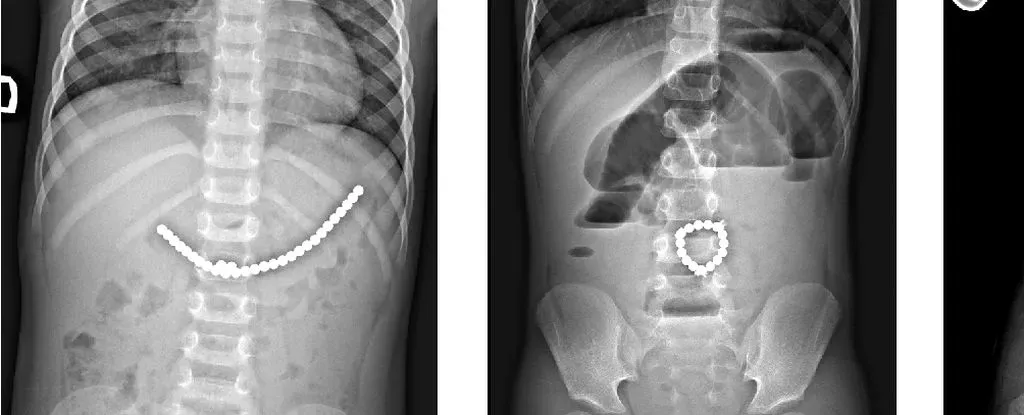

儿童吞食小型磁珠后的 X 光片。来源:Da?kevi?iūt? et al.,2017

值得关注的是,74.3%

的伤害事件发生在社会经济背景较好的儿童身上,这些孩子可能更容易接触到强磁力玩具套装,且家长对风险认知更高。然而,社会经济背景较差的儿童一旦发生此类事件,伤势往往更为严重,需要手术干预、更长的住院时间以及再次入院治疗。